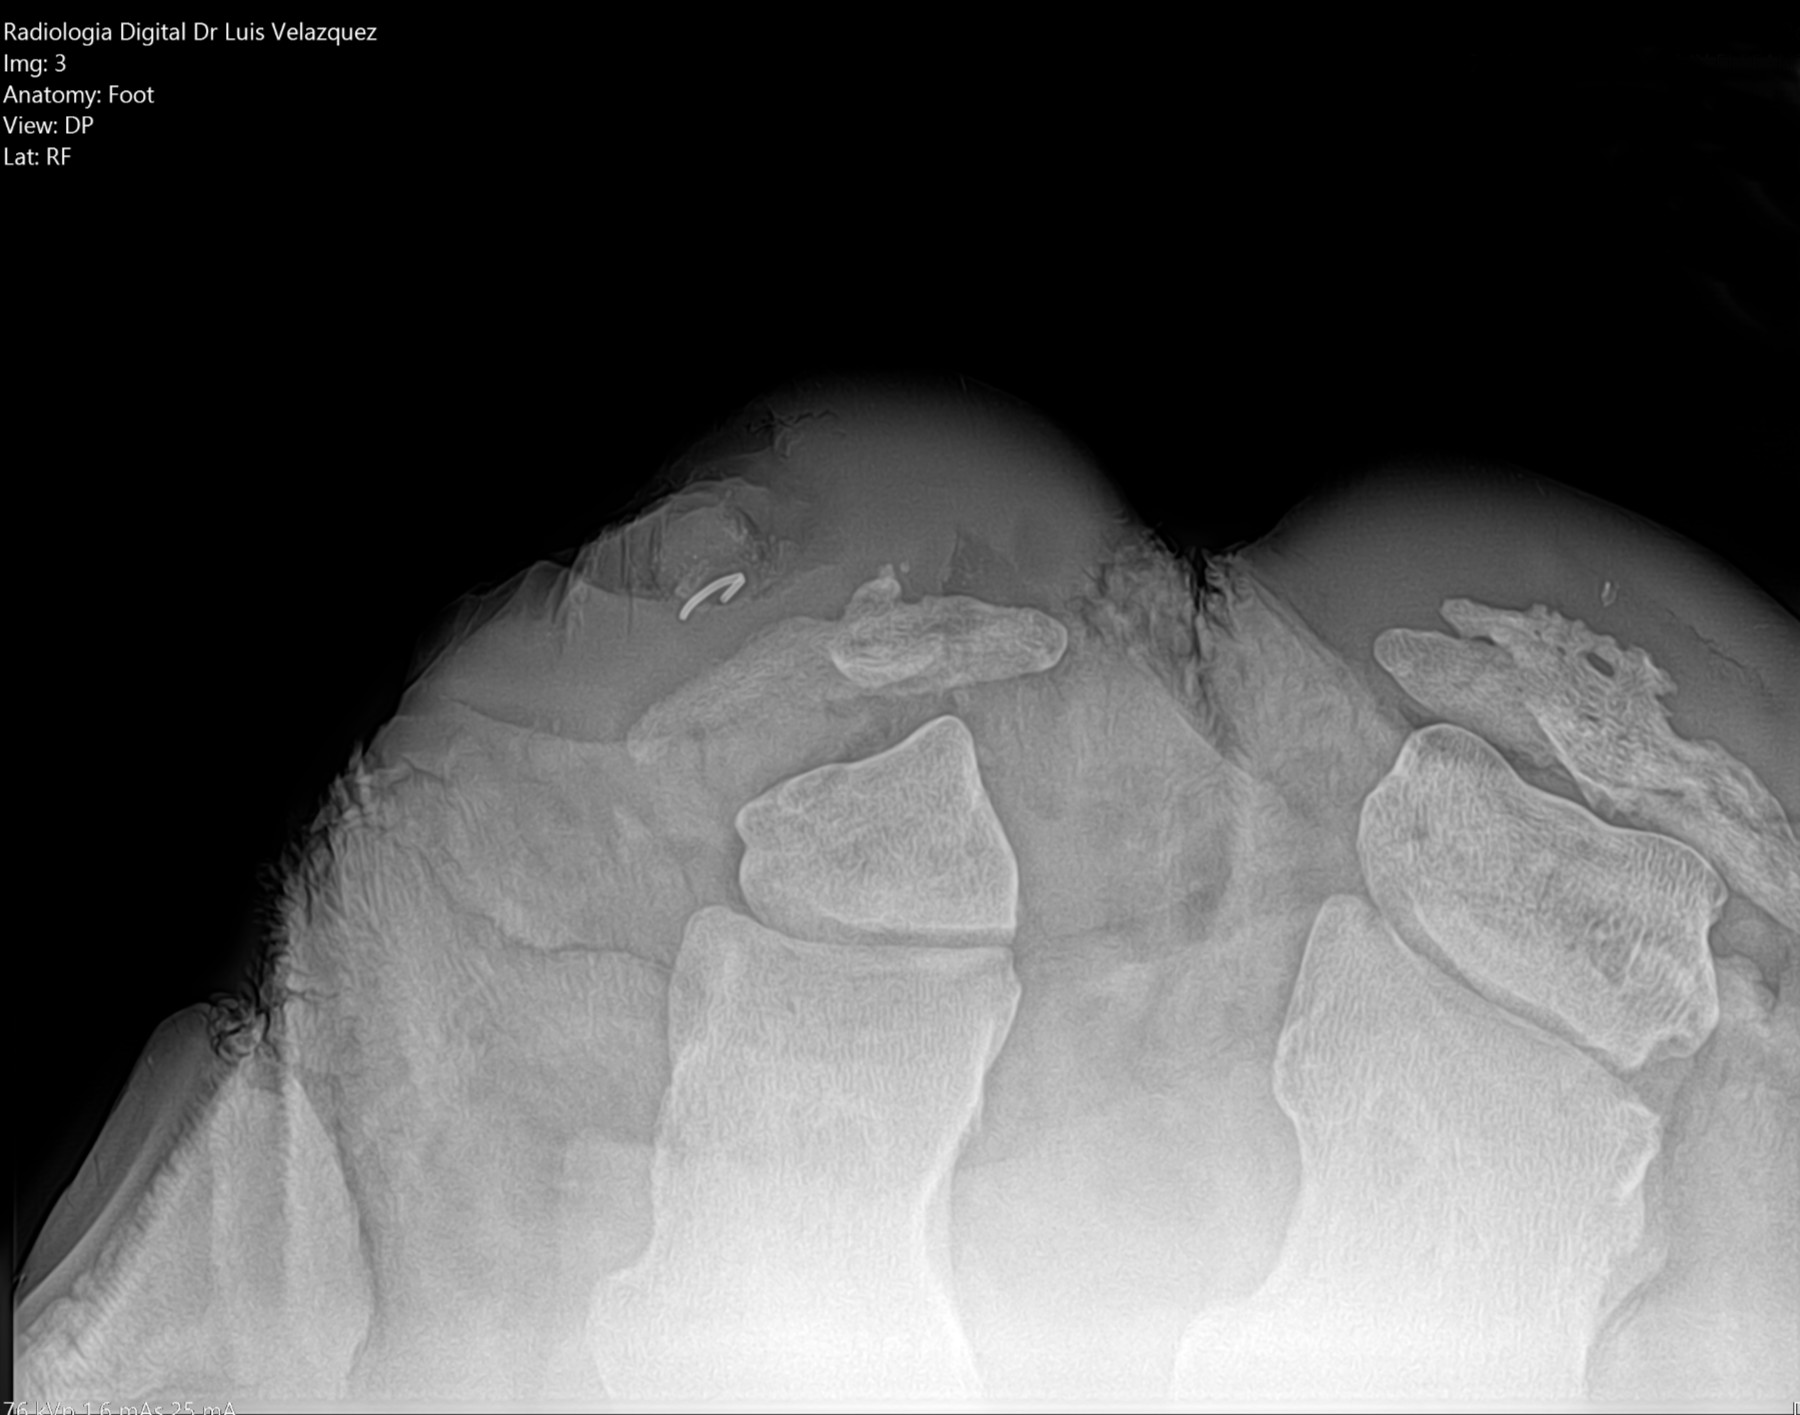

Radiología Digital como Herramienta Complementaria en el Dictamen de Bienes Muebles